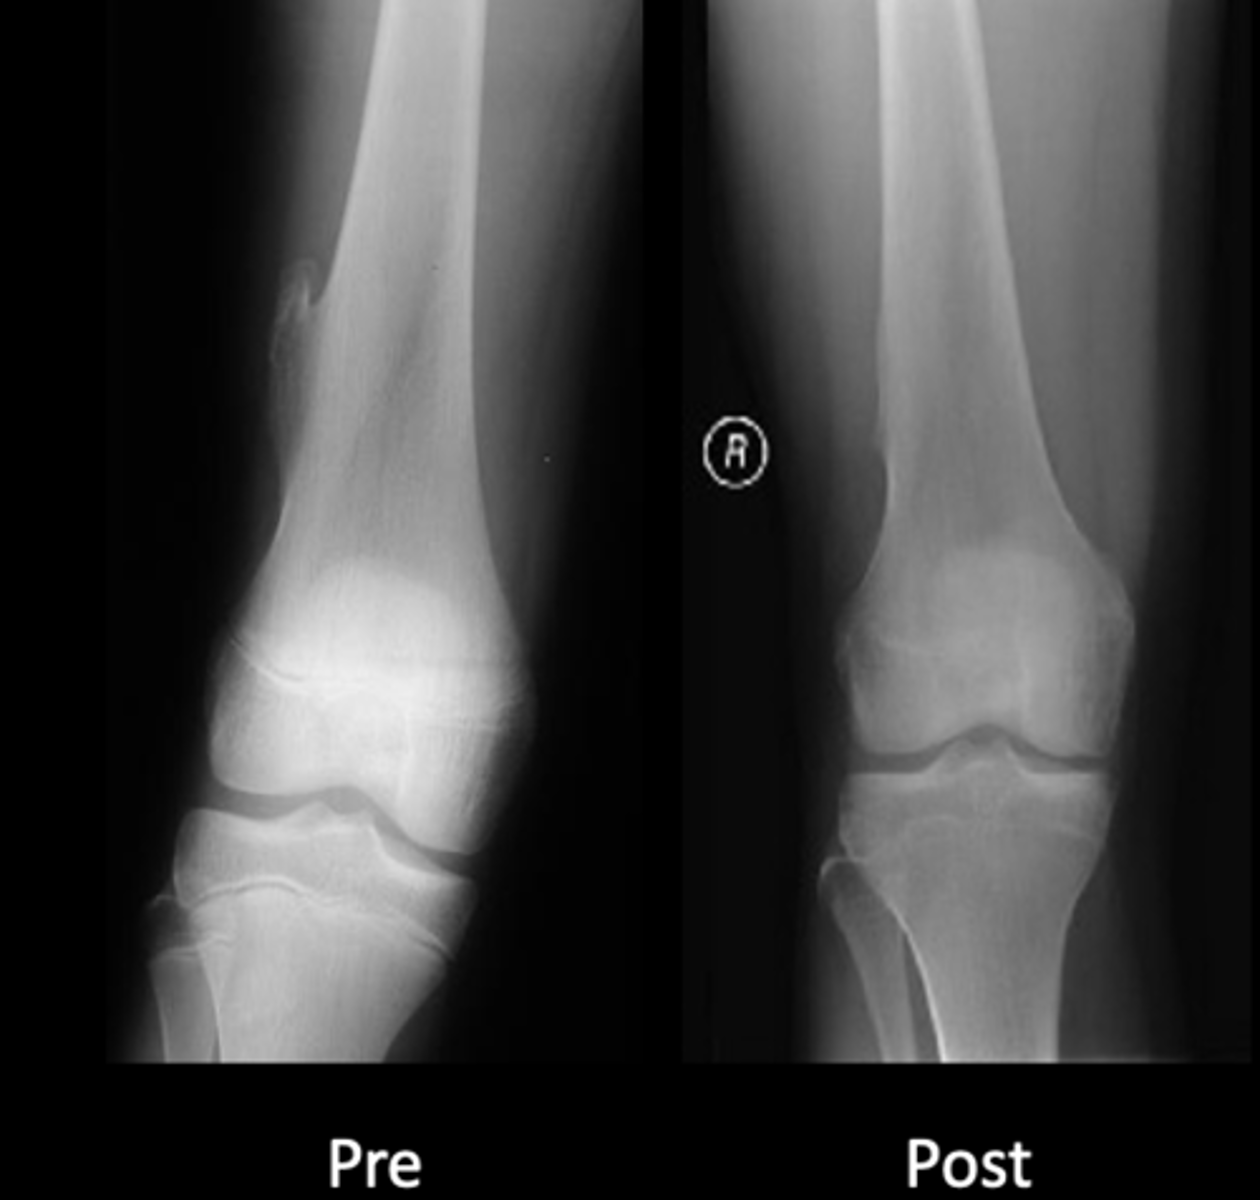

Geographic bone blister

ID radiographic feature of non-ossifying fibroma indicated by top arrow

<p>ID radiographic feature of non-ossifying fibroma indicated by top arrow</p>

59

New cards

Septations

ID radiographic feature of non-ossifying fibroma indicated by bottom arrow

<p>ID radiographic feature of non-ossifying fibroma indicated by bottom arrow</p>

60

Pathologic fracture

Non-ossifying fibroma with _____

<p>Non-ossifying fibroma with _____</p>